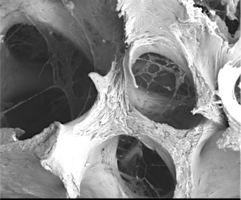

По внешнему виду представляет собой пористый губчатый блок номинального размера.

2. Поверхность и структура материала для изготовления биоимплантатов